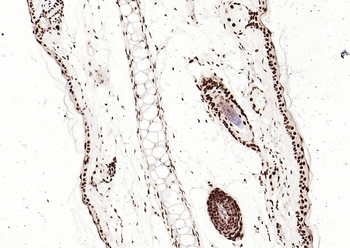

100 μl, 200 μl, 50 μlSMAD7 Rabbit Polyclonal Antibody [orb500819]

FC, ICC, IF, IHC-Fr, IHC-P, WB

Bovine, Porcine

Human, Mouse, Rat

Rabbit

Polyclonal

Unconjugated

100 μl, 200 μl, 50 μlPhospho-Smad3 (Ser213) Rabbit Polyclonal Antibody [orb106193]